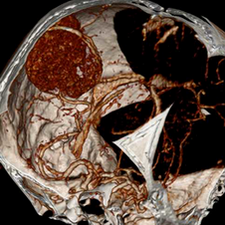

标题: CT25808:男,48岁,头痛多年,近段时间头痛加重伴步态不稳 [打印本页]

标题: CT25808:男,48岁,头痛多年,近段时间头痛加重伴步态不稳

平扫:右颞顶叶病灶呈等低密度伴大面积水肿,脑室受压变形。增强:病灶显著强化。考虑淋巴瘤或黑色素瘤。

1)不排除黑色素瘤可能;建议行mri检查。2)大脑镰下疝。3)脑积水(梗阻性)。